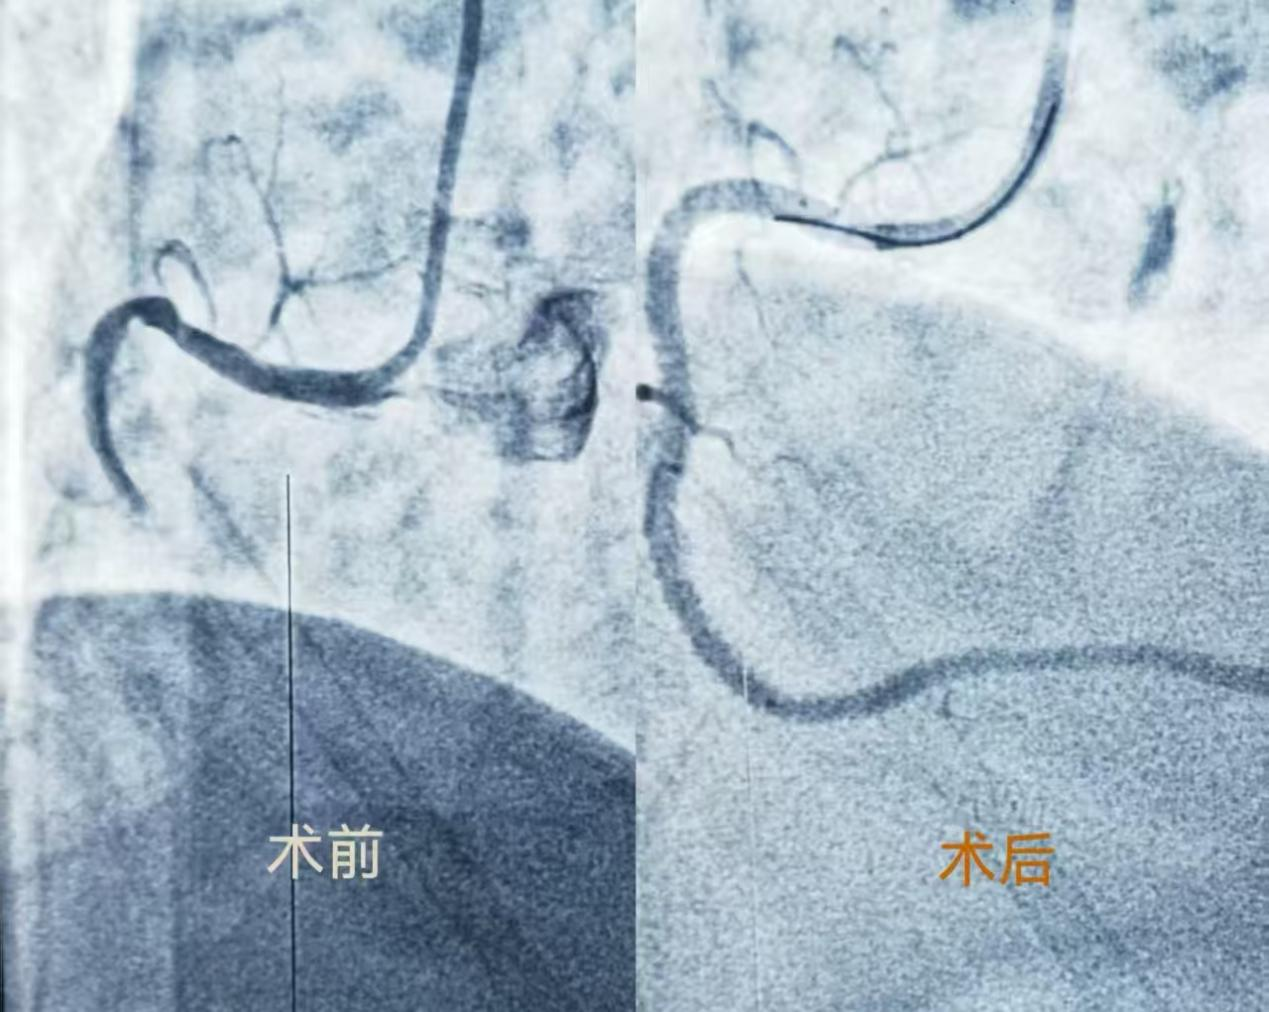

近一个月来,老何先生又发作胸闷,经当地药物治疗后不仅无缓解,反而逐渐加重,并出现心率紊乱等危急情况,使其不禁想起了二十三年前救过他的地区医院(现在的广西科技大学第一附属医院),毅然要求子女从广州送他回到我院就医,这才上演了开头的动人一幕。当老何先生看清眼前这位已是两鬓斑白的主任医师正是当年救他一命的何医师时,久别重逢的亲切感瞬间冲散了病痛的阴霾,病房里你一言我一语,聊过往的救治点滴,话如今的生活近况,无半分生疏,唯有岁月沉淀的真挚情谊。 经充分评估病情后,何汉康主任亲自走上手术台,造影检查显示老何先生本次发病为右冠脉闭塞,病变是主支闭塞段特别长伴钙化,伴右室支严重狭窄,手术不仅难度大而且风险高。凭借丰富的临床经验和精湛的介入技术,何主任精心采用对侧造影明确血管走向、血管内超声寻找进攻点和真腔、导丝升降级交换通过不同的闭塞段、平行导丝避免方向偏离等技术,成功开通了闭塞的右冠脉,并保住了粗大的右室支,手术取得圆满成功。让老何先生再次从危急病情中康复。